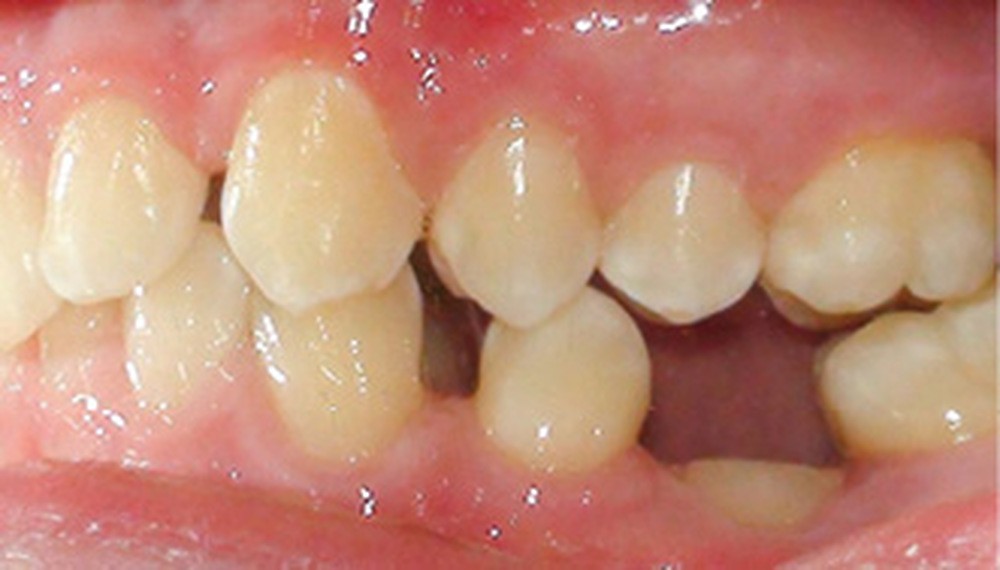

Quand un traitement orthodontique est indiqué dans le cadre de la persistance d’une molaire temporaire, l’orthodontiste doit toujours choisir entre deux solutions : maintenir ou fermer l’espace d’agénésie. Malheureusement, il est parfois confronté à une indication de maintien de l’espace d’agénésie, alors que la dent temporaire ne peut pas être maintenue jusqu’à la fin de la croissance (pour cause de caries, de réinclusion sévère, de perte, etc.) (fig. 1). La pose d’un mainteneur d’espace en fin de traitement est nécessaire, mais rien ne maintient l’os jusqu’à la fin de la croissance et la pose implantaire ! Les patients se retrouvent alors obligés de recourir à des préparations osseuses préimplantaires parfois lourdes. Le but de cet article est de proposer des solutions de maintien du volume osseux après avulsion de la deuxième molaire temporaire.

L’infraclusion de la molaire temporaire, et dans son cas extrême sa réinclusion, est le résultat d’une ankylose de la dent. Cette dent ne pourra plus suivre la croissance de l’os maxillaire ou mandibulaire et ainsi le plan d’occlusion. La molaire temporaire ne présentant pas de germe définitif sous-jacent, elle s’ankylose fréquemment à un stade plus ou moins avancé de l’individu et de la croissance des maxillaires.